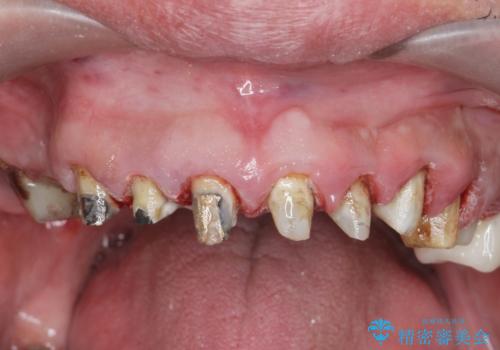

- 前医で行った前歯セラミック形態の改善、常に腫れぼったく歯ブラシの際に出血のある前歯部の治療を希望され来院されました。

前医により、前歯は歯ぐきの奥深くまで形成されこのままの状態でセラミックをやりかえたとしても歯ぐきの腫れの改善は難しい状況です。